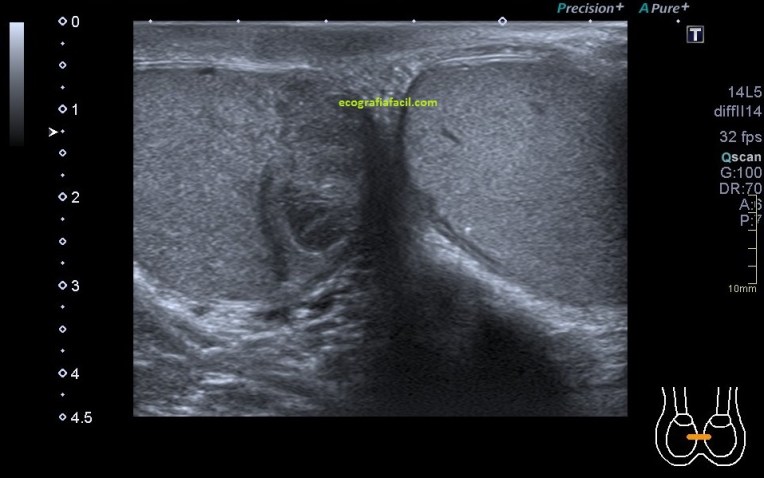

1.Tendón del biceps, cabeza larga.

Situada en la corredera bicipital, vas a ver el bíceps como una estructura hiperecogénica, redondeada situado en el valle de la corredera. Observa como la imagen superior indica ausencia de líquido y normalidad y la inferior relación entre la anatomía y la patología donde el líquido rodea el tendón en relación con una posible tenosinovitis.